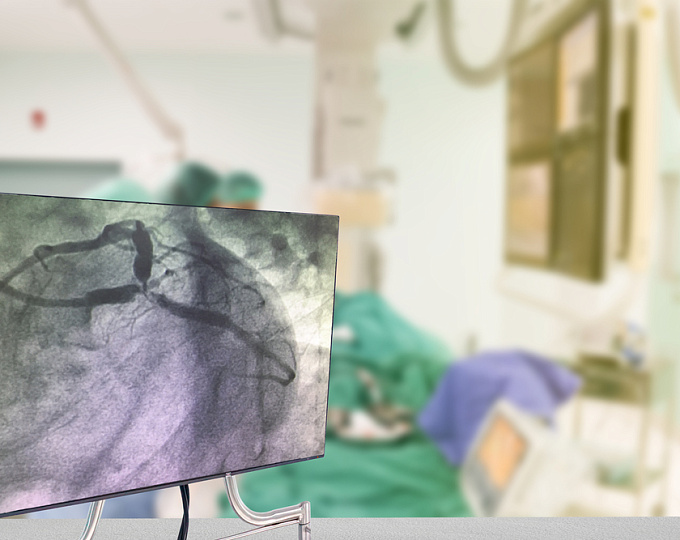

ЧКВ у пациентов с ишемической сердечной недостаточностью: ждать ли улучшения прогноза?

Актуальность Целесообразность выполнения чрескожного коронарного вмешательства (ЧКВ) у пациентов с ишемической сердечной недостаточностью до конца не определена.

В связи с чем целью рандомизированного исследования REVIVED-BCIS2 была оценка эффективности ЧКВ в улучшении прогноза у пациентов с ишемической сердечной недостаточностью. Методы Участниками исследования были пациенты с ишемической хронической сердечной недостаточностью (фракция выброса ≤35%), жизнеспособным миокардом и тяжелым поражением коронарных артерий. В соотношении 1:1 они рандомизировались в группы ЧКВ и оптимальной медикаментозной терапии, и только оптимальной медикаментозной терапии.

Первичной конечной точкой была смерть от всех причин и госпитализации по поводу сердечной недостаточности. Результаты Заключение Таким образом, у пациентов с ишемической сердечной недостаточностью выполнение ЧКВ не сопровождается улучшением прогноза. В очередной раз ЧКВ оказалось не лучше оптимальной медикаментозной терапии в неострой сит